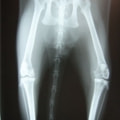

症例:右大腿骨遠位部の肉腫 クランバー・スパニエル 9歳 雌(未避妊)

2か月前から右後肢の完全挙上が認められ、消炎剤による内科治療で改善しないとのことで、他院から紹介来院した。

レントゲン検査

骨生検および病理組織検査

レントゲン検査所見から、骨もしくはその周囲組織に発生した腫瘍の可能性が考えられたため、病変部の細胞診検査およびジャムシディ生検針を用いた病変の骨生検を実施した。病理組織検査の結果、非上皮性の悪性腫瘍である“肉腫”と診断された。

内科治療に反応が乏しい四肢の跛行や疼痛は、本症例のように腫瘍が原因となっていることがあるため、レントゲン検査、骨生検等積極的に原因追及のための検査を実施することが必要である。骨の破壊を起こす悪性腫瘍は、非常に強い痛みを伴い、消炎鎮痛剤を用いても痛みを抑えることが困難となる。痛みの除去および腫瘍の治療のために断脚手術や抗がん剤等が必要となる場合があり、似た症状を示す整形外科疾患等とは治療法・予後が異なるため、その鑑別は重要である。